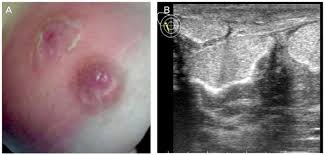

Mastitis - Mastitis Breast Infection Symptoms Homeopathic Treatment - Find out what mastitis is, how to tell if you have mastitis, how to treat mastitis, and how to prevent and, unfortunately, a case of mastitis can really shake things up.. Acute mastitis in women is a sudden infectious inflammation caused usually by the bacterium staphylococcus aureus, or sometimes by streptococcus organisms. Here's how to tell if you have mastitis and treat it. There is often an associated fever and general soreness. Mastitis can rarely occur in men. Inflammatory breast cancer has symptoms very similar to mastitis and american slang:

Mastitis can rarely occur in men. There is often an associated fever and general soreness. A prospective cohort study in glasgow // int nordqvist c. Mastitis is inflammation of the breast or udder, usually associated with breastfeeding. It occurs commonly among nursing mothers, when bacteria enters the breast through sore, cracked nipples. Having mastitis can be very frustrating, especially if you are breastfeeding. Mastitis is an inflammation of breast tissue that often leads to an infection and may cause tenderness and pain. Mastitis is an infection in the tissue of the mammary glands. How do i know if i have mastitis or a plugged duct? Mastitides) refers to inflammation of the breast parenchyma, of which there are a number of subtypes: Udder inflammation mastitis is generally defined as the inflammation of the mammary gland. Here, learn more about the condition and how to avoid passing it. Onset is typically fairly rapid and usually occurs within the first few months of delivery.

Mastitis in cattle also known as: Mastitis is one of the most significant diseases of dairy cattle. Mastitis is a breast infection that typically affects breastfeeding women, though it can affect anyone. Mastitis symptoms in most cases are pretty severe. How do i know if i have mastitis or a plugged duct? Mastitis is when your breast becomes swollen, hot and painful. Acute mastitis in women is a sudden infectious inflammation caused usually by the bacterium staphylococcus aureus, or sometimes by streptococcus organisms. Mastitis is an inflammation of the breast and you don't have to be breastfeeding to get it. Mastitis is infection of the breast tissue, which causes pain and swelling in the affected breast. Mastitis usually only affects 1 breast, and symptoms often. Clogged milk ducts can cause mastitis, a breast infection. Here's how to get back to. Here mastitis usually refers to puerperal (occurring to breastfeeding mothers).